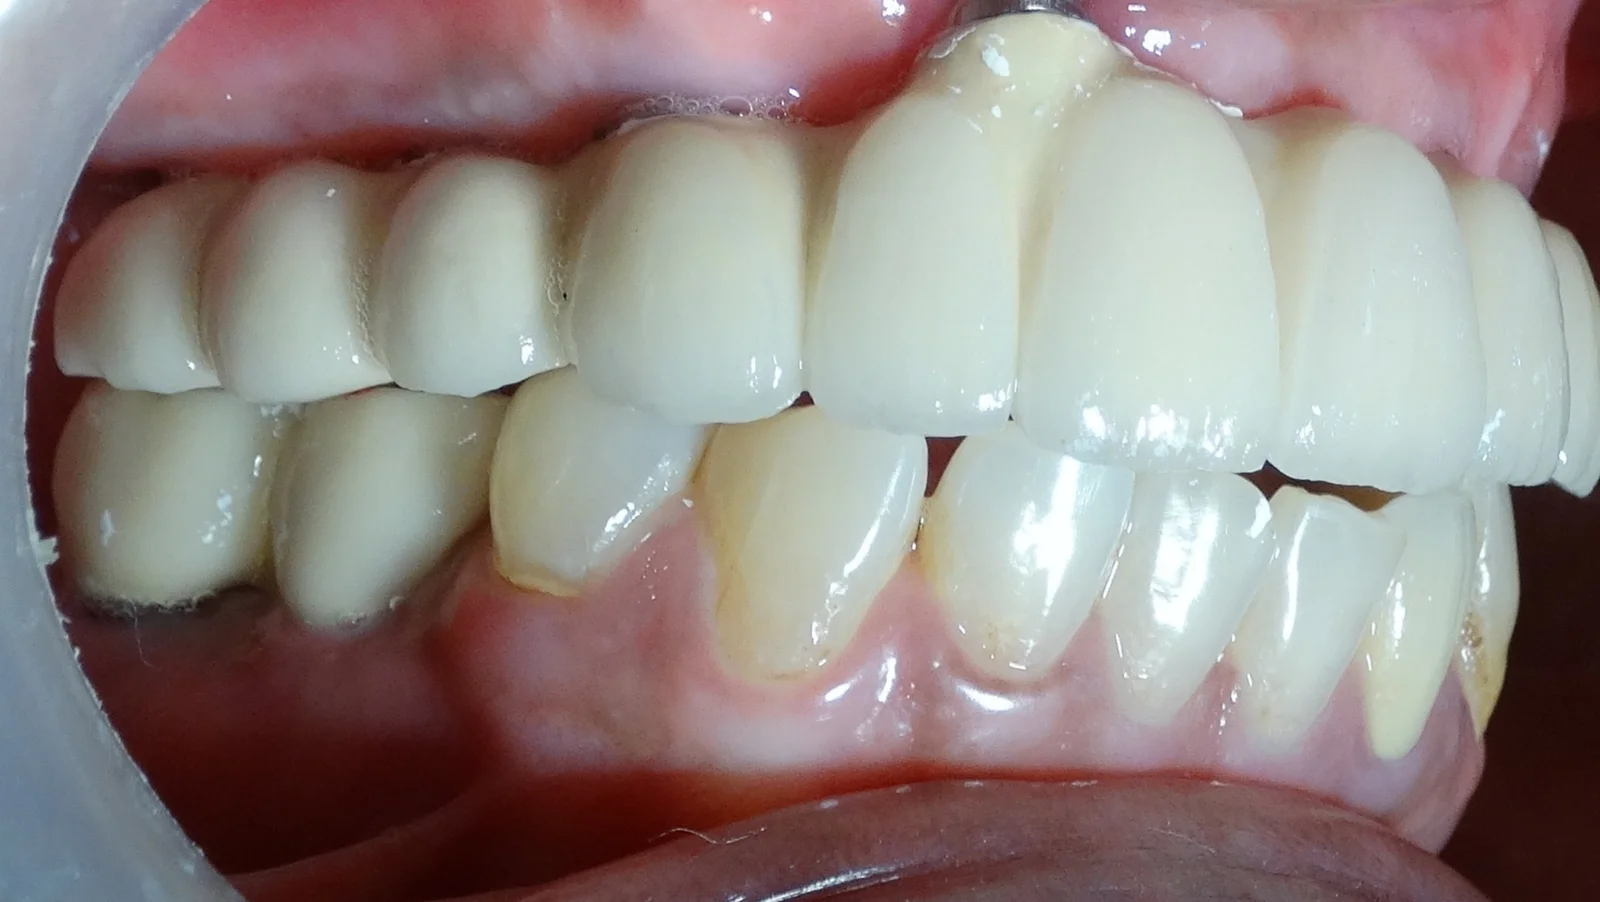

Full Mouth Rehabilitation

Implant Supported Fixed Teeth

Replacing all missing teeth with a permanent, fixed prosthesis that mimics the look, feel, and function of natural teeth. Explore our clinical transformations below.